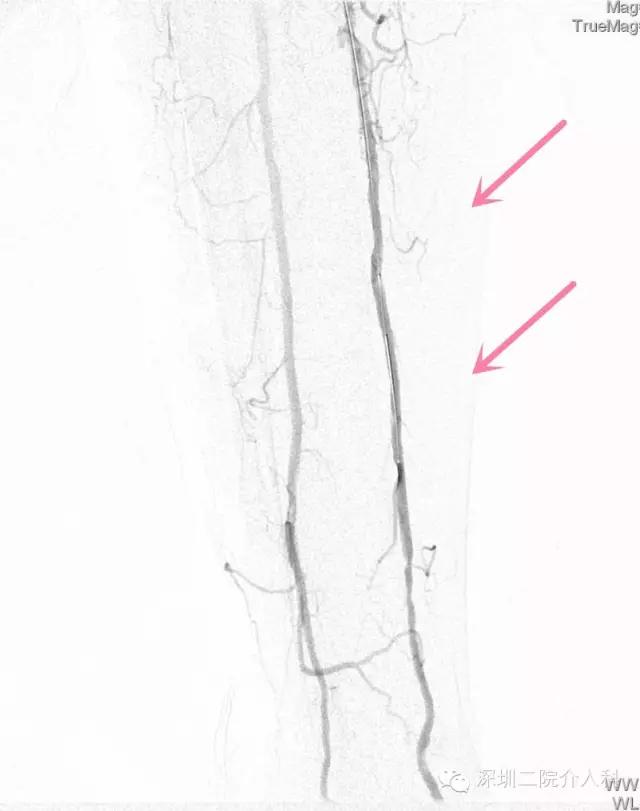

经球囊扩张后造影通畅,狭窄闭塞段消失: